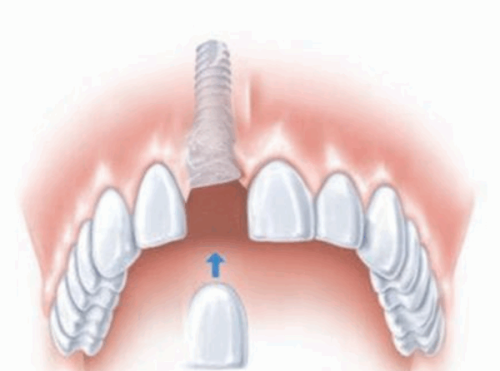

- 種植團隊:由高建嶺、朱延康醫生領銜,團隊擁有豐富的臨床經驗,累計完成超2000例種植病例,擅長數字化微創種植技術及All - on - 4等半口/全口複雜種植。

- 數字化種植:依托CBCT數據及口掃技術,進行術前模擬規劃,可能應用數字化導板,旨在提升種植位置的準確度,縮短手術時間。